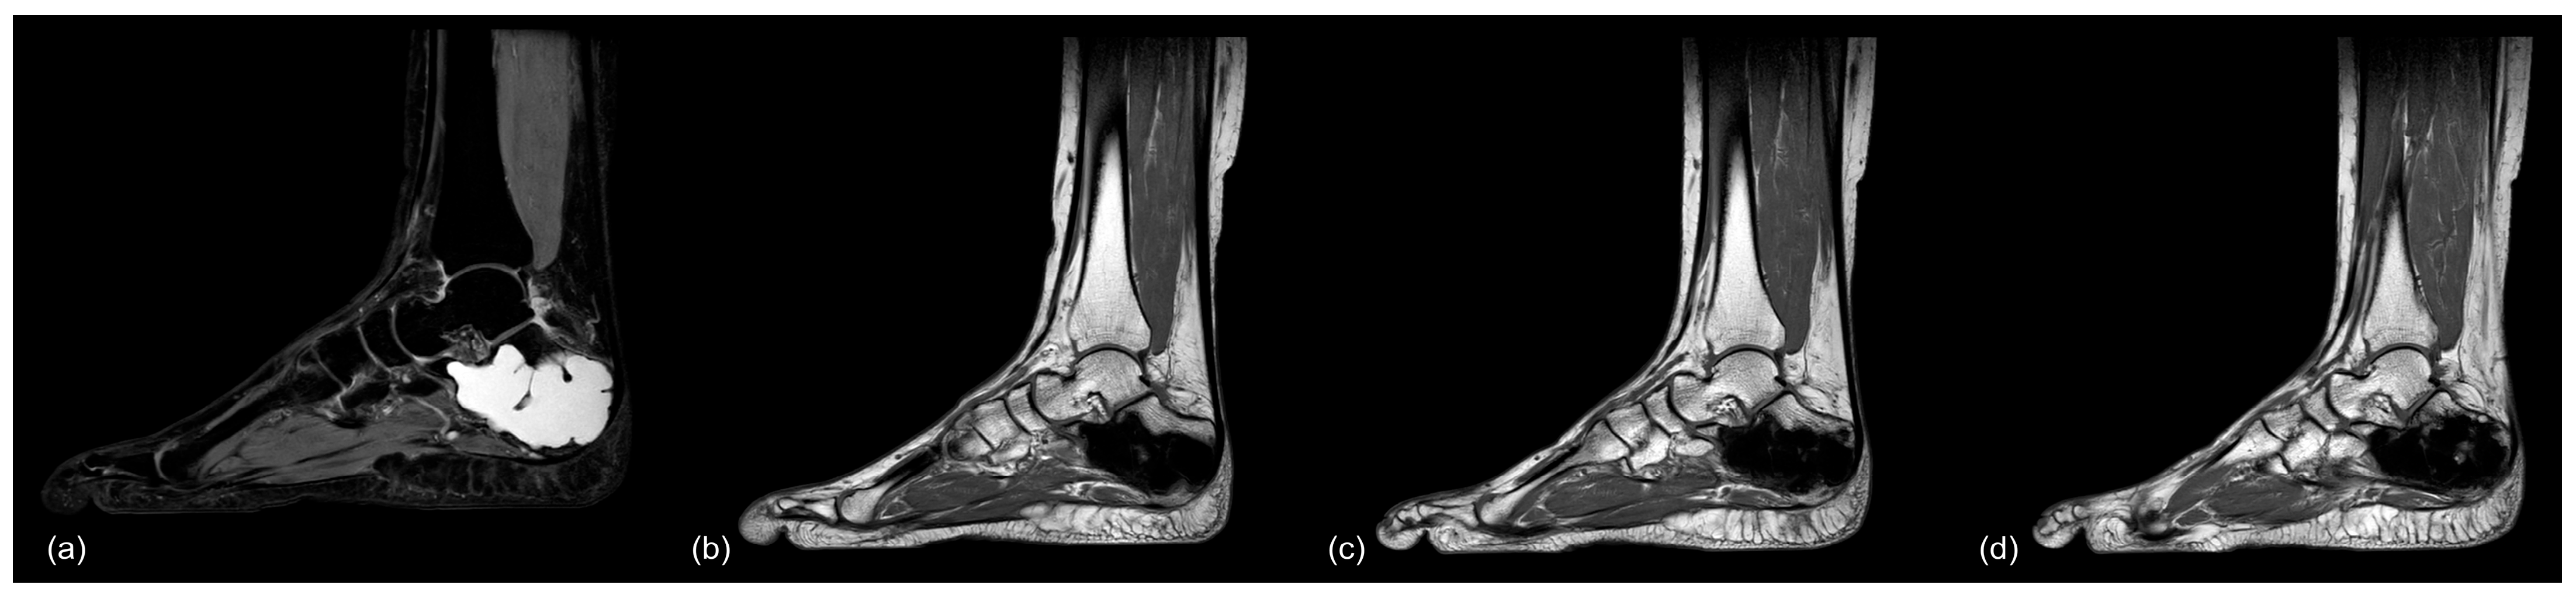

Figure 11.

MR-imaging of case 26: (a) preop (PD TSE sag), (b) 6.5 months postop (T1 TSE sag), (c) 13 months postop (T1 TSE sag), and (d) 40 months postop (T1 TSE sag), showing no signs of osseous remodeling after more than 3 years postoperatively.